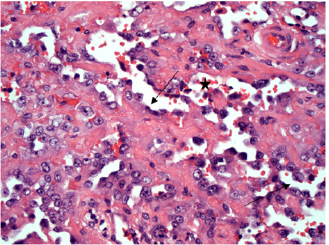

Moderate to marked cellular pleomorphism and nuclear atypia were seen in all cases. Mitoses per 10HPF (2.73 mm2), varied from 3 to 34 per HPF, with case 4 displaying the highest number of mitoses and the only case with metastatic spread (Fig. 4). Solar elastosis was seen in five cases (Fig. 5).

In the two horses diagnosed with conjunctival angiosarcoma, the histopathological findings reflected malignant conjunctival neoplasms that were poorly differentiated with regards to lineage. Both of these neoplasms had a solid epithelioid growth pattern and an absence of vascular channel formation, but vascular lineage was suspected given the location and H&E morphology of the tumour, accompanying perivascular lymphonodular aggregates and absence of overlying surface epithelial pathology with regards to dysplastic or neoplastic changes to indicate carcinoma (Fig. 6). IHC was performed in these two cases in an attempt to rule out the differential diagnosis of carcinoma and confirm vascular lineage as a requirement for further tumour identification (Fig. 7).

Fig. 6. (A) Case 4 gross pathology photomicrograph of a solid, poorly differentiated angiosarcoma, note the cream-coloured cut surface. (B) Histopathology photomicrograph, case 4, note the highly cellular and solid presentation with a lack of vasculature and red blood cells.

In Figure 8, a conjunctival haemangiosarcoma displays the more “classical” gross appearance of haemangiosarcoma; an exophytic mass with red appearance to both the cut surface and on histopathology. Blood-filled channels lined with neoplastic cells provide the tumour with a red appearance. Although clinically appearing as a discrete mass, the invasive nature of this tumour type can be seen with neoplastic cells infiltrating the cornea outside the mass. Contrast this to Figure (6), a poorly differentiated, solid angiosarcoma. Whilst still marginally exophytic, the gross appearance was cream/pale coloured, and histopathology revealed a lack of blood vessels. The tumour was solid in appearance with poorly differentiated cells making classification difficult. This highlights the importance of haemangiosarcoma as a differential for conjunctival masses in a horse, even if their appearance is not grossly red.